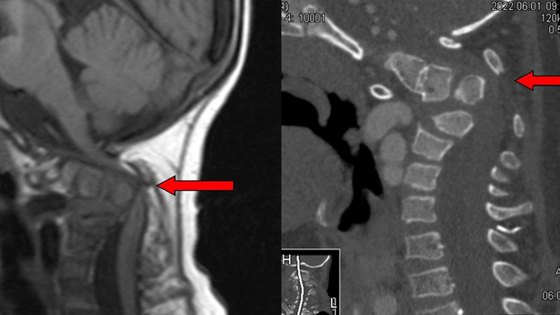

«У ребенка было диагностировано критическое сдавление спинного мозга, при малейшем ударе или физической нагрузке пациенту грозил полный паралич и даже смерть. Пациенту было проведено три сложных и длительных высокотехнологичных операции, две из которых проходили в два-три этапа. Нейрохирурги установили пациенту двойную фиксирующую металлоконструкцию в шейном отделе позвоночника», — говорится в сообщении. В лечении пациента принимали участие руководитель Центра имени Илизарова Александр Бурцев и врачи Ольга Сергеенко и Максим Древаль.